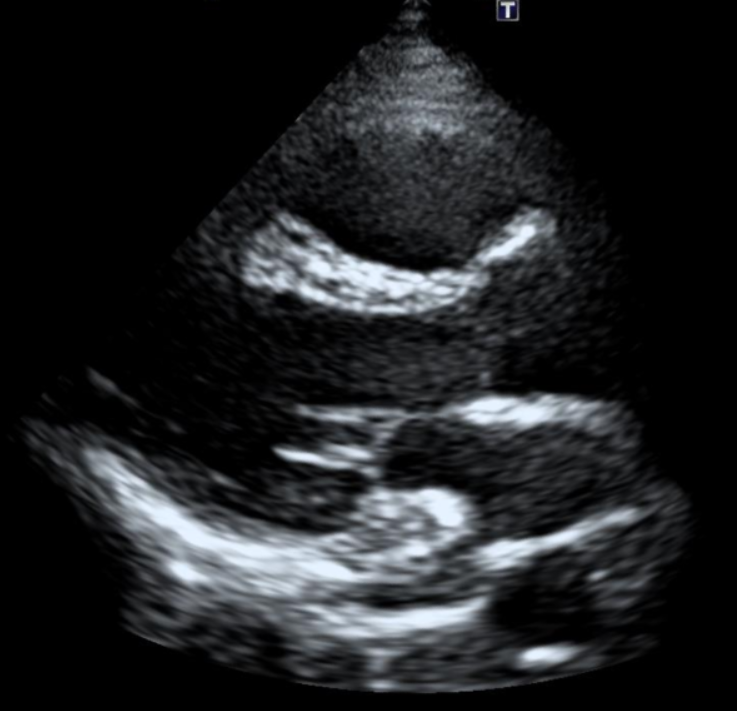

2. 심장초음파

• 심장초음파 검사 결과: 정상 심장초음파 검사 결과: 정상